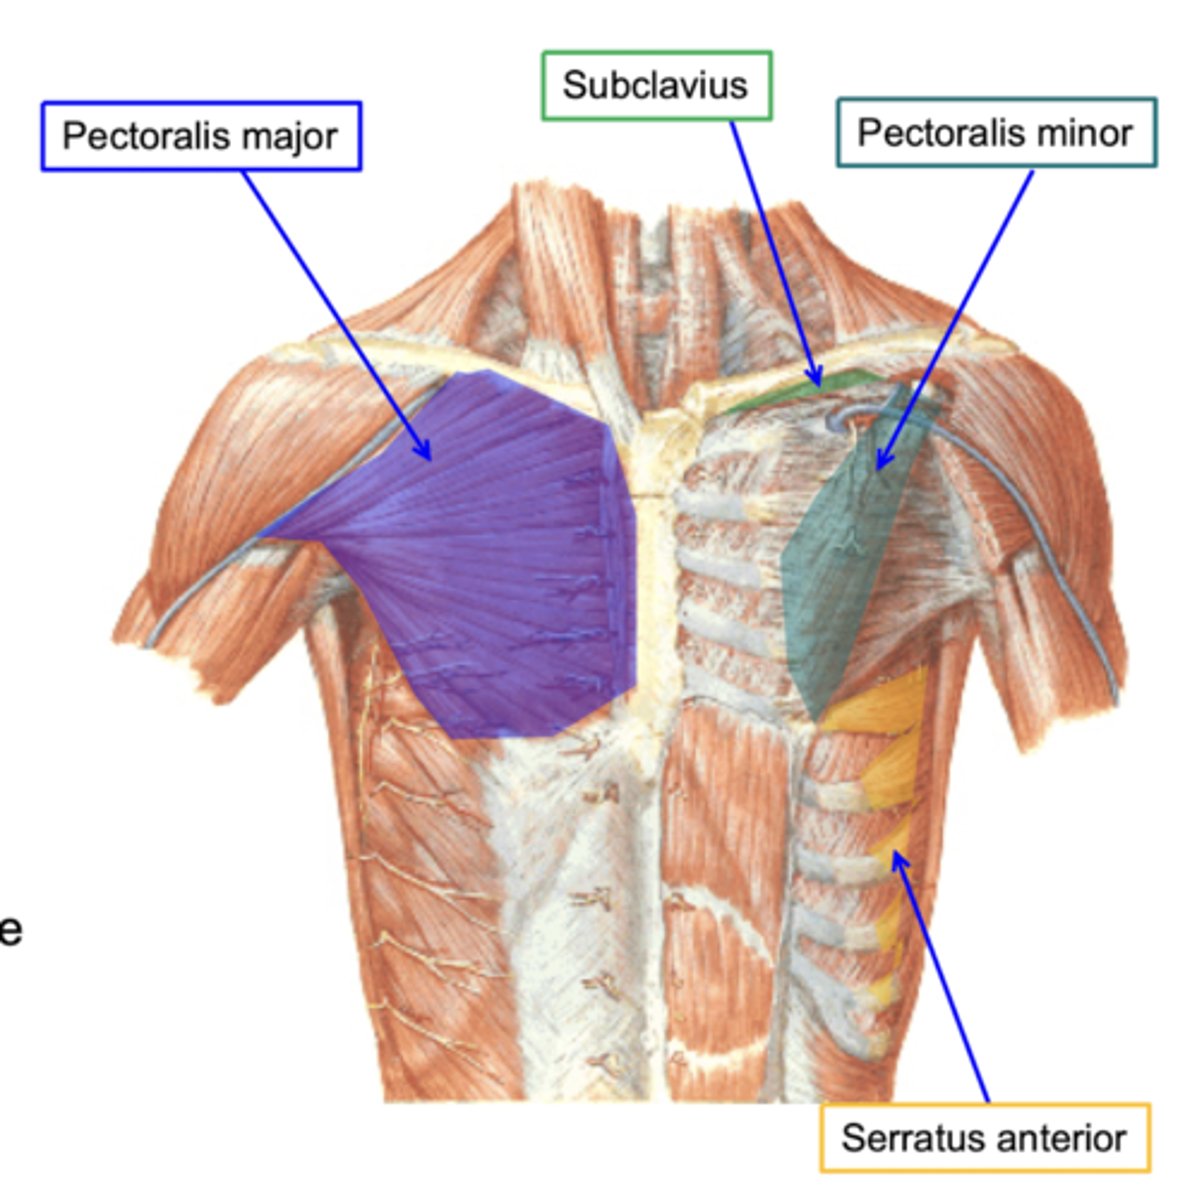

(Muscles of the pectoral region:) Anterior axioappendicular muscles

These muscles move the pectoral girdle

-Contains Pectoralis major, Pectoralis minor, Subclavius muscle, Serratus anterior

(Anterior axioappendicular muscles:) Pectoralis major

-Adduction and medial rotation of humerus. Draws scapula anteriorly and inferiorly

-Medial (C8 – T1) & lateral (C5 – C7) pectoral n.

-Delto-pectoral groove: formed between pectoralis major and deltoid, allows passage for the cephalic vein

(Anterior axioappendicular muscles:) Pectoralis minor

-Stabilizes scapula

-Medial pectoral n. (C8 - T1)

-Forms a bridge with the coracoid process allowing the passage of nerves and vessels to the arm

(Anterior axioappendicular muscles:) Subclavius muscle

-Anchors and depresses clavicle

-Nerves to subclavius (C5 - C6)

-Protects subclavian vessels and brachial plexus in case of fracture of the clavicle

(Anterior axioappendicular muscles:) Serratus anterior

-Protracts and stabilizes scapula

-Long thoracic n. (C5 - C7)